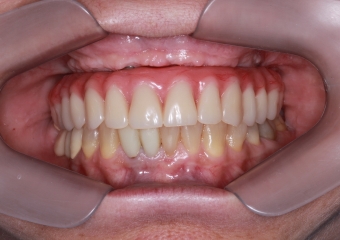

Sorriso Inicial

Sorriso Final com a prótese provisória